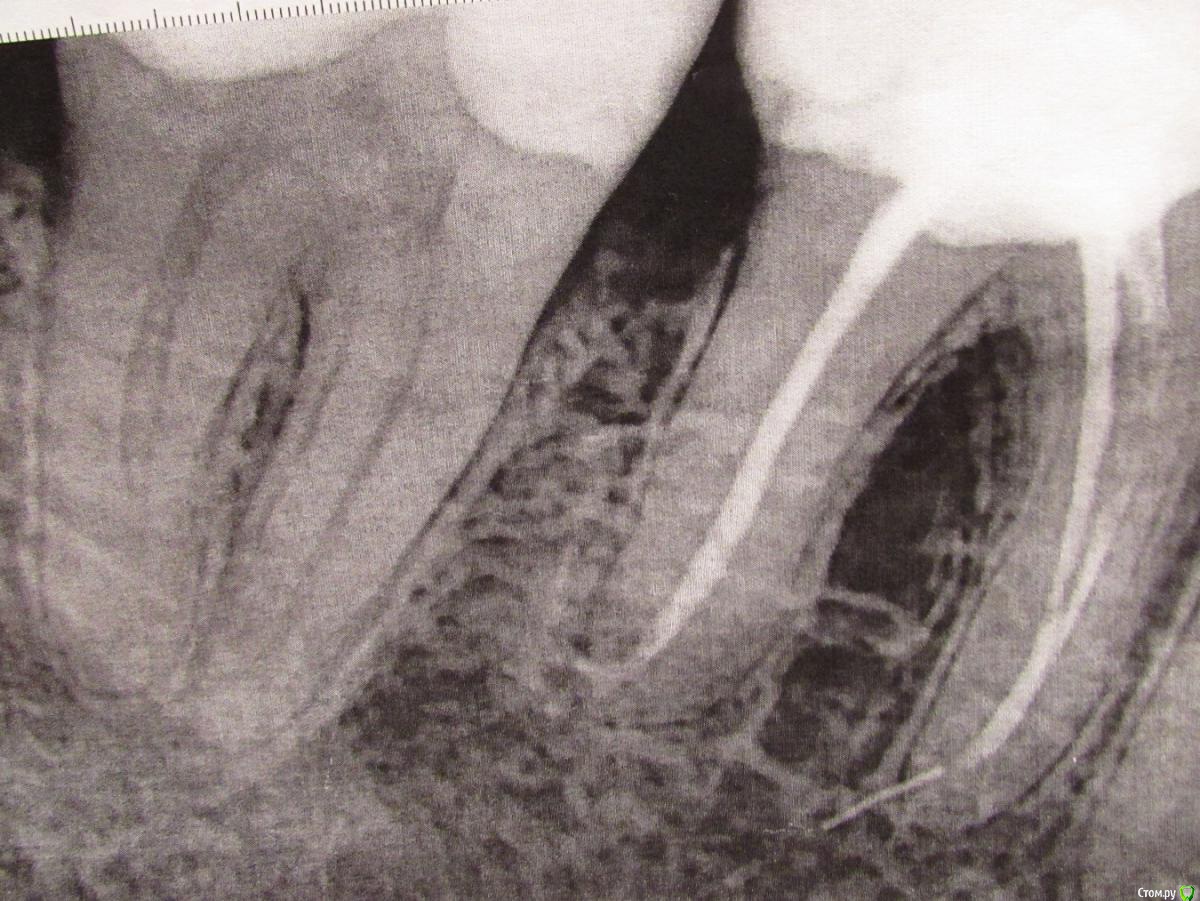

Подскажите, пожалуйста, действительно ли бывает такой пломбировочный материал для коней, который не виден на рентгеновских снимках? Я делала протезирование коронками с металлическими культевыми вкладками. Когда примеряли вкладки, доктор спиливал длинную "ножку". Зачем он изначально сделал ее именно такой длинной не знаю. Но стало быть под эту "ножку" был убран пломбировочный материла из канала. После окончания работ я попросила сделать контрольный снимок. Сделали. И я увидела, что канал пустой. Я спросила доктора, почему канал пустой. На это он мне ответил (как мне показалось, заметно нервничая), что канал не пустой, а там есть материла (или цемент, не помню точно), но его просто не видно на снимке. Вот такой рентгенонейтральный, что-ли материал. У меня есть поводы беспокоится или доктор говорит правду? На первом снимке зуб до ортопедических работ. Спасибо.